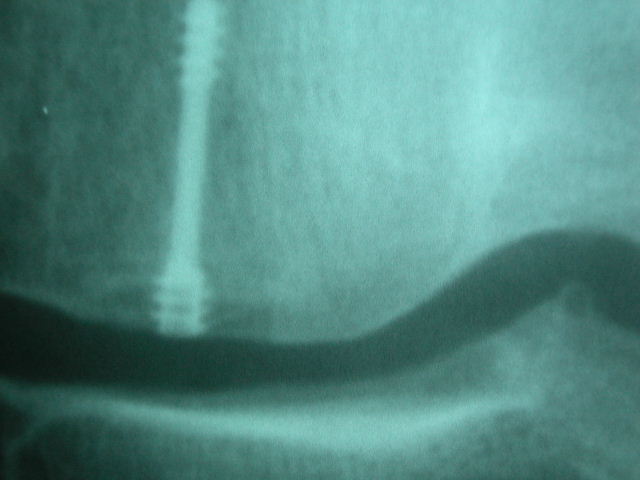

osteosíntesis fractura fémur